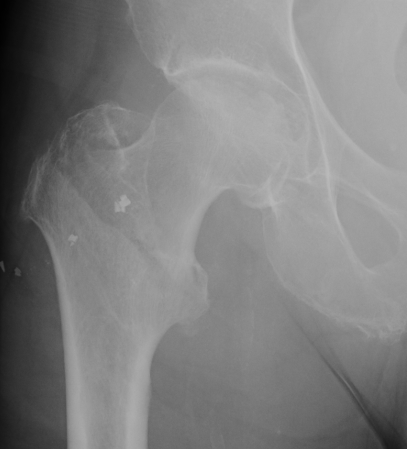

Definition

Fracture which extends between the trochanters of the proximal femur

Extra capsular / well vascularized

Evans Classification

Two main types

- Type 1 Intertrochanteric

- Type 2 Reverse Oblique

Type 1 Intertrochanteric

2 part undisplaced

2 part displaced

3 part without posterolateral support (GT fracture)

3 part without posteromedial support (LT fracture)

4 part without posterolateral or posteromedial support